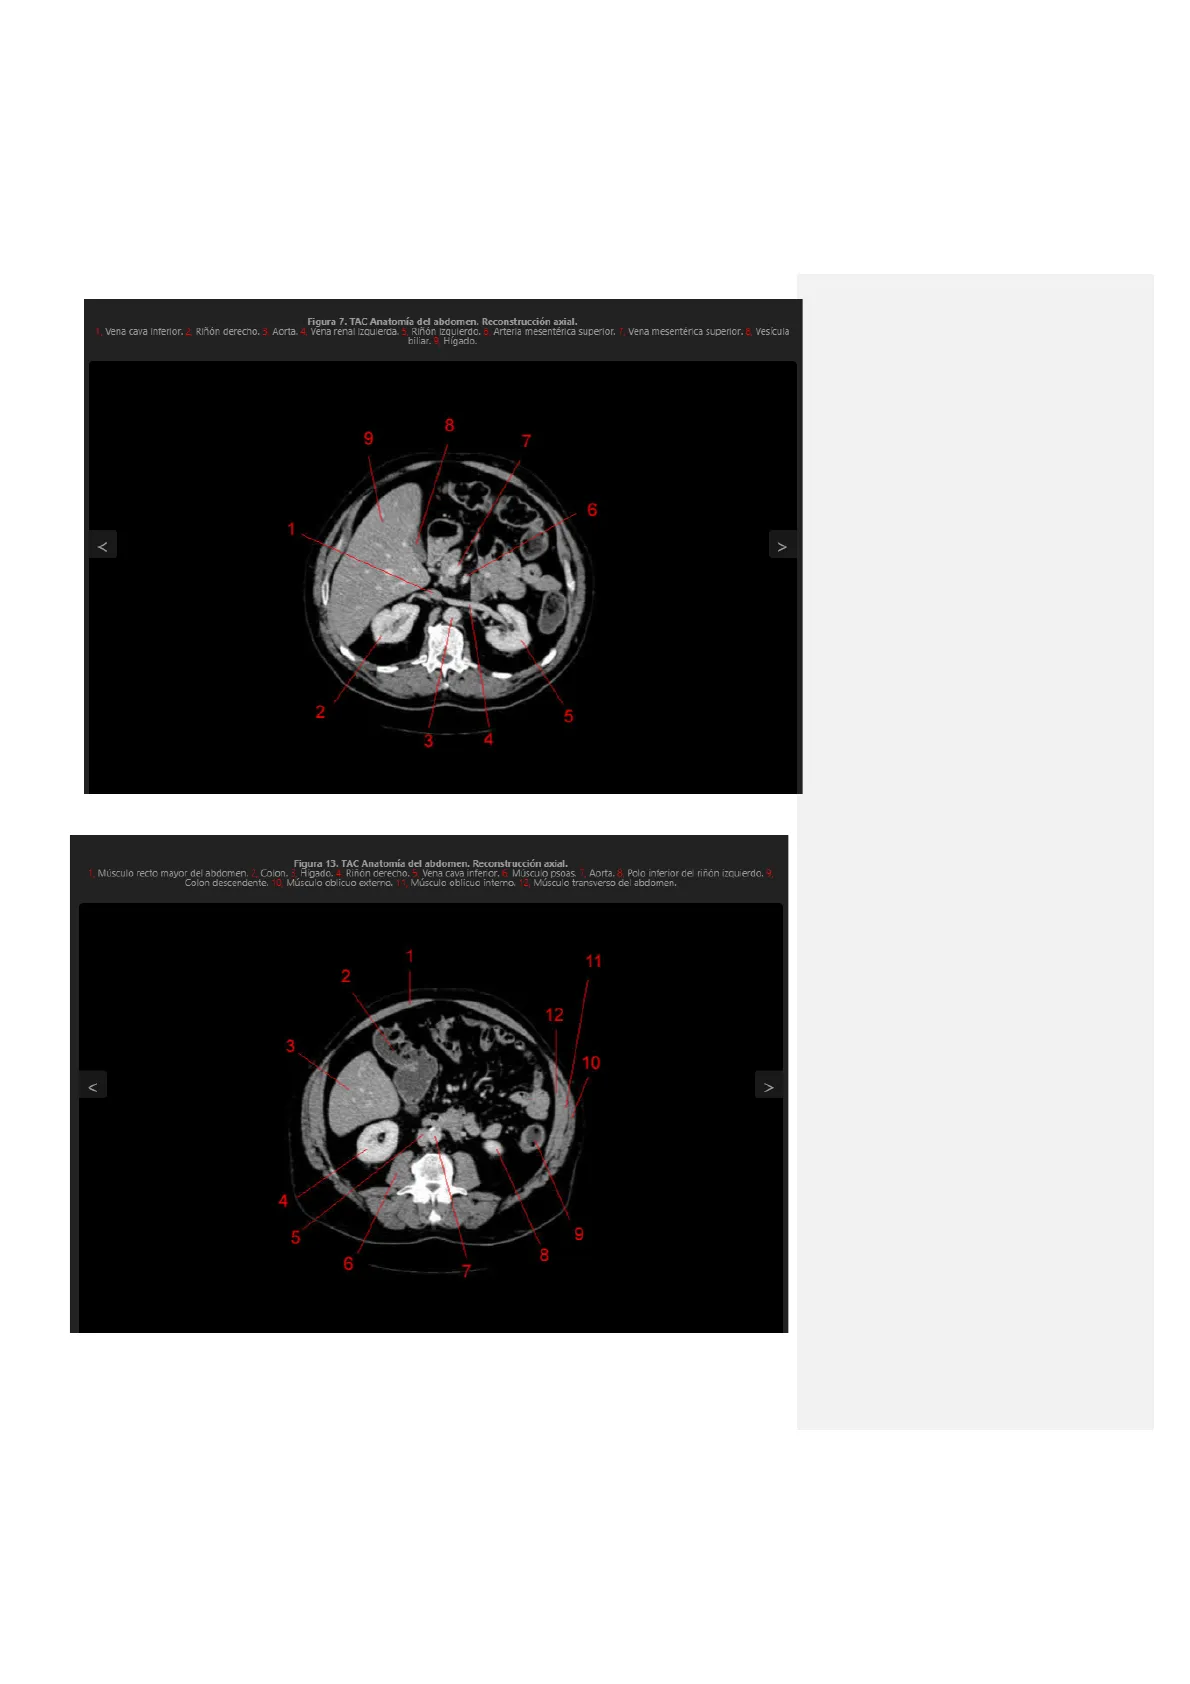

Figura 7. TAC Anatomía del abdomen. Reconstrucción axial. 1, Vena cava inferior. 2, Riñón derecho. 3, Aorta, 4, Vena renal izquierda. 5, Riñón izquierdo. 6, Arteria mesentérica superior. 7, Vena mesentérica superior. 8, Vesícula biliar. 9, Hígado. 8 9 7 6 1 ‹ > 2 5 3 4 En la realidad esta al contrario. Figura 13. TAC Anatomía del abdomen. Reconstrucción axial. 1, Músculo recto mayor del abdomen. 2, Colon. 3, Hígado. 4, Riñón derecho. 5, Vena cava inferior. 6, Músculo psoas. 7, Aorta. 8, Polo inferior del riñón izquierdo. 9, Colon descendente. 10, Musculo oblicuo externo. 11, Musculo oblicuo interno. 12, Músculo transverso del abdomen. 1 11 2 12 3 10 V > 4 9 5 8 6 7